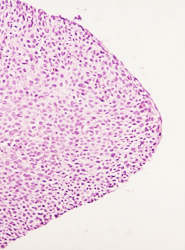

El resultado de una valoración colposcópica de paciente con lesión displásica siempre será confirmado por el estudio histopatológico que realiza el médico anatomopatólogo (estudio de la biopsia tomada en la colposcopía) . A continuación presentamos imágenes histológicas con sus diagnósticos.

• NIC 1 (Displasia leve de cérvix)

• NIC I.- Acantosis regular, anisocitosis y anisocariosis leves. Proceso inflamatorio en la lámina propia severo reactivo.

• NIC I.- No obstante la cariomegalia, la cromatina esta dispuesta en grumos finos.

• NIC I.- Anisocitosis y anisocariosis leves. Estroma ricamente vascularizado.